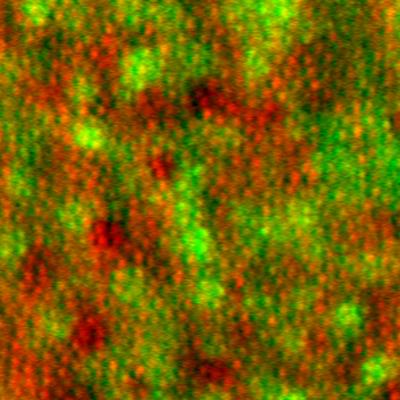

Retinal pigment epithelial cells imaged  using adaptive optics

Retinal pigment epithelial cells imaged noninvasively in a living human eye using adaptive optics. Image generated using a combination of multiply-scattered light (red) and intrinsic near-infrared autofluorescence (green).

Read the associated publication.